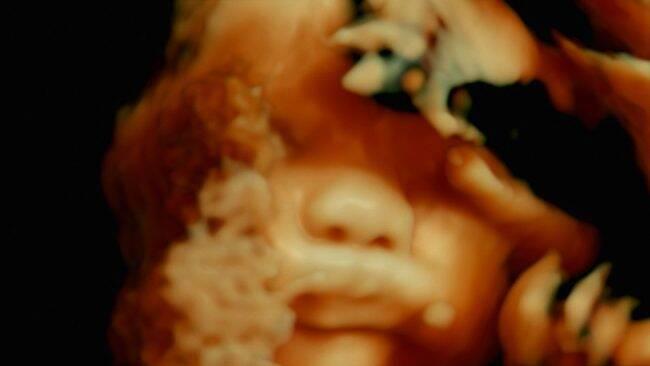

En dépit des apparences, le dégoût ou l’horreur ne sont que momentanés. De Humani corporis fabrica nous fait sentir pleinement humains : des humains qui partagent intensément du cinéma. Car nous palpons dans la salle obscure ce qui affole ponctuellement tel ou tel voisin : qui la césarienne, qui un tournevis vissé au cerveau, qui la trouée d’une pupille. Mais l’on s’aperçoit vite que c’est l’acte d’inciser ou de pénétrer (l’œil, le crâne, le ventre ou le côlon) qui suscite la répulsion. Une fois que l’œil du spectateur se glisse au sein du corps, il s’abreuve avec la joie d’un enfant des beautés du minuscule. Ce Monde sans Dieu est nourri d’une infinie curiosité, sans idéologie préconçue ni émotion facile face au fameux « miracle du vivant ». Nous sommes soumis par le montage aux exigences et au rythme des soignants. Lors de la naissance d’un enfant, la réunion attendue avec la mère est furtive, voire périphérique : il faut d’abord inciser les restes de l’épais cordon qui rattachait l’enfant aux limbes.

Le film noue et renoue deux échelles, l’infiniment petit et l’infiniment grand, conformément là encore à un second élément topique du discours philosophique sur l’Homme : l’ordre du cosmos fait écho à l’organisation anatomique. À ceci près que dans De humani corporis fabrica, le cosmos est un corps politique en souffrance : celui des hôpitaux dans lesquels les cinéastes ont tourné. Il est fait d’artères, de nœuds, et de couloirs sans fin dans lesquels les malades errent, avec plus ou moins d’inquiétude. À cet égard, le rapprochement entre le corps et l’hôpital, quoique prometteur, paraît trop ébauché pour mener vers une réflexion véritablement politique, car l’assimilation du premier au microcosme et du second au macrocosme tend à gommer la différence de nature qui existe entre leurs failles respectives. D’autant que le film, assez long, n’évite pas tout à fait le risque d’un lisse égrenage de séquences d’opération.